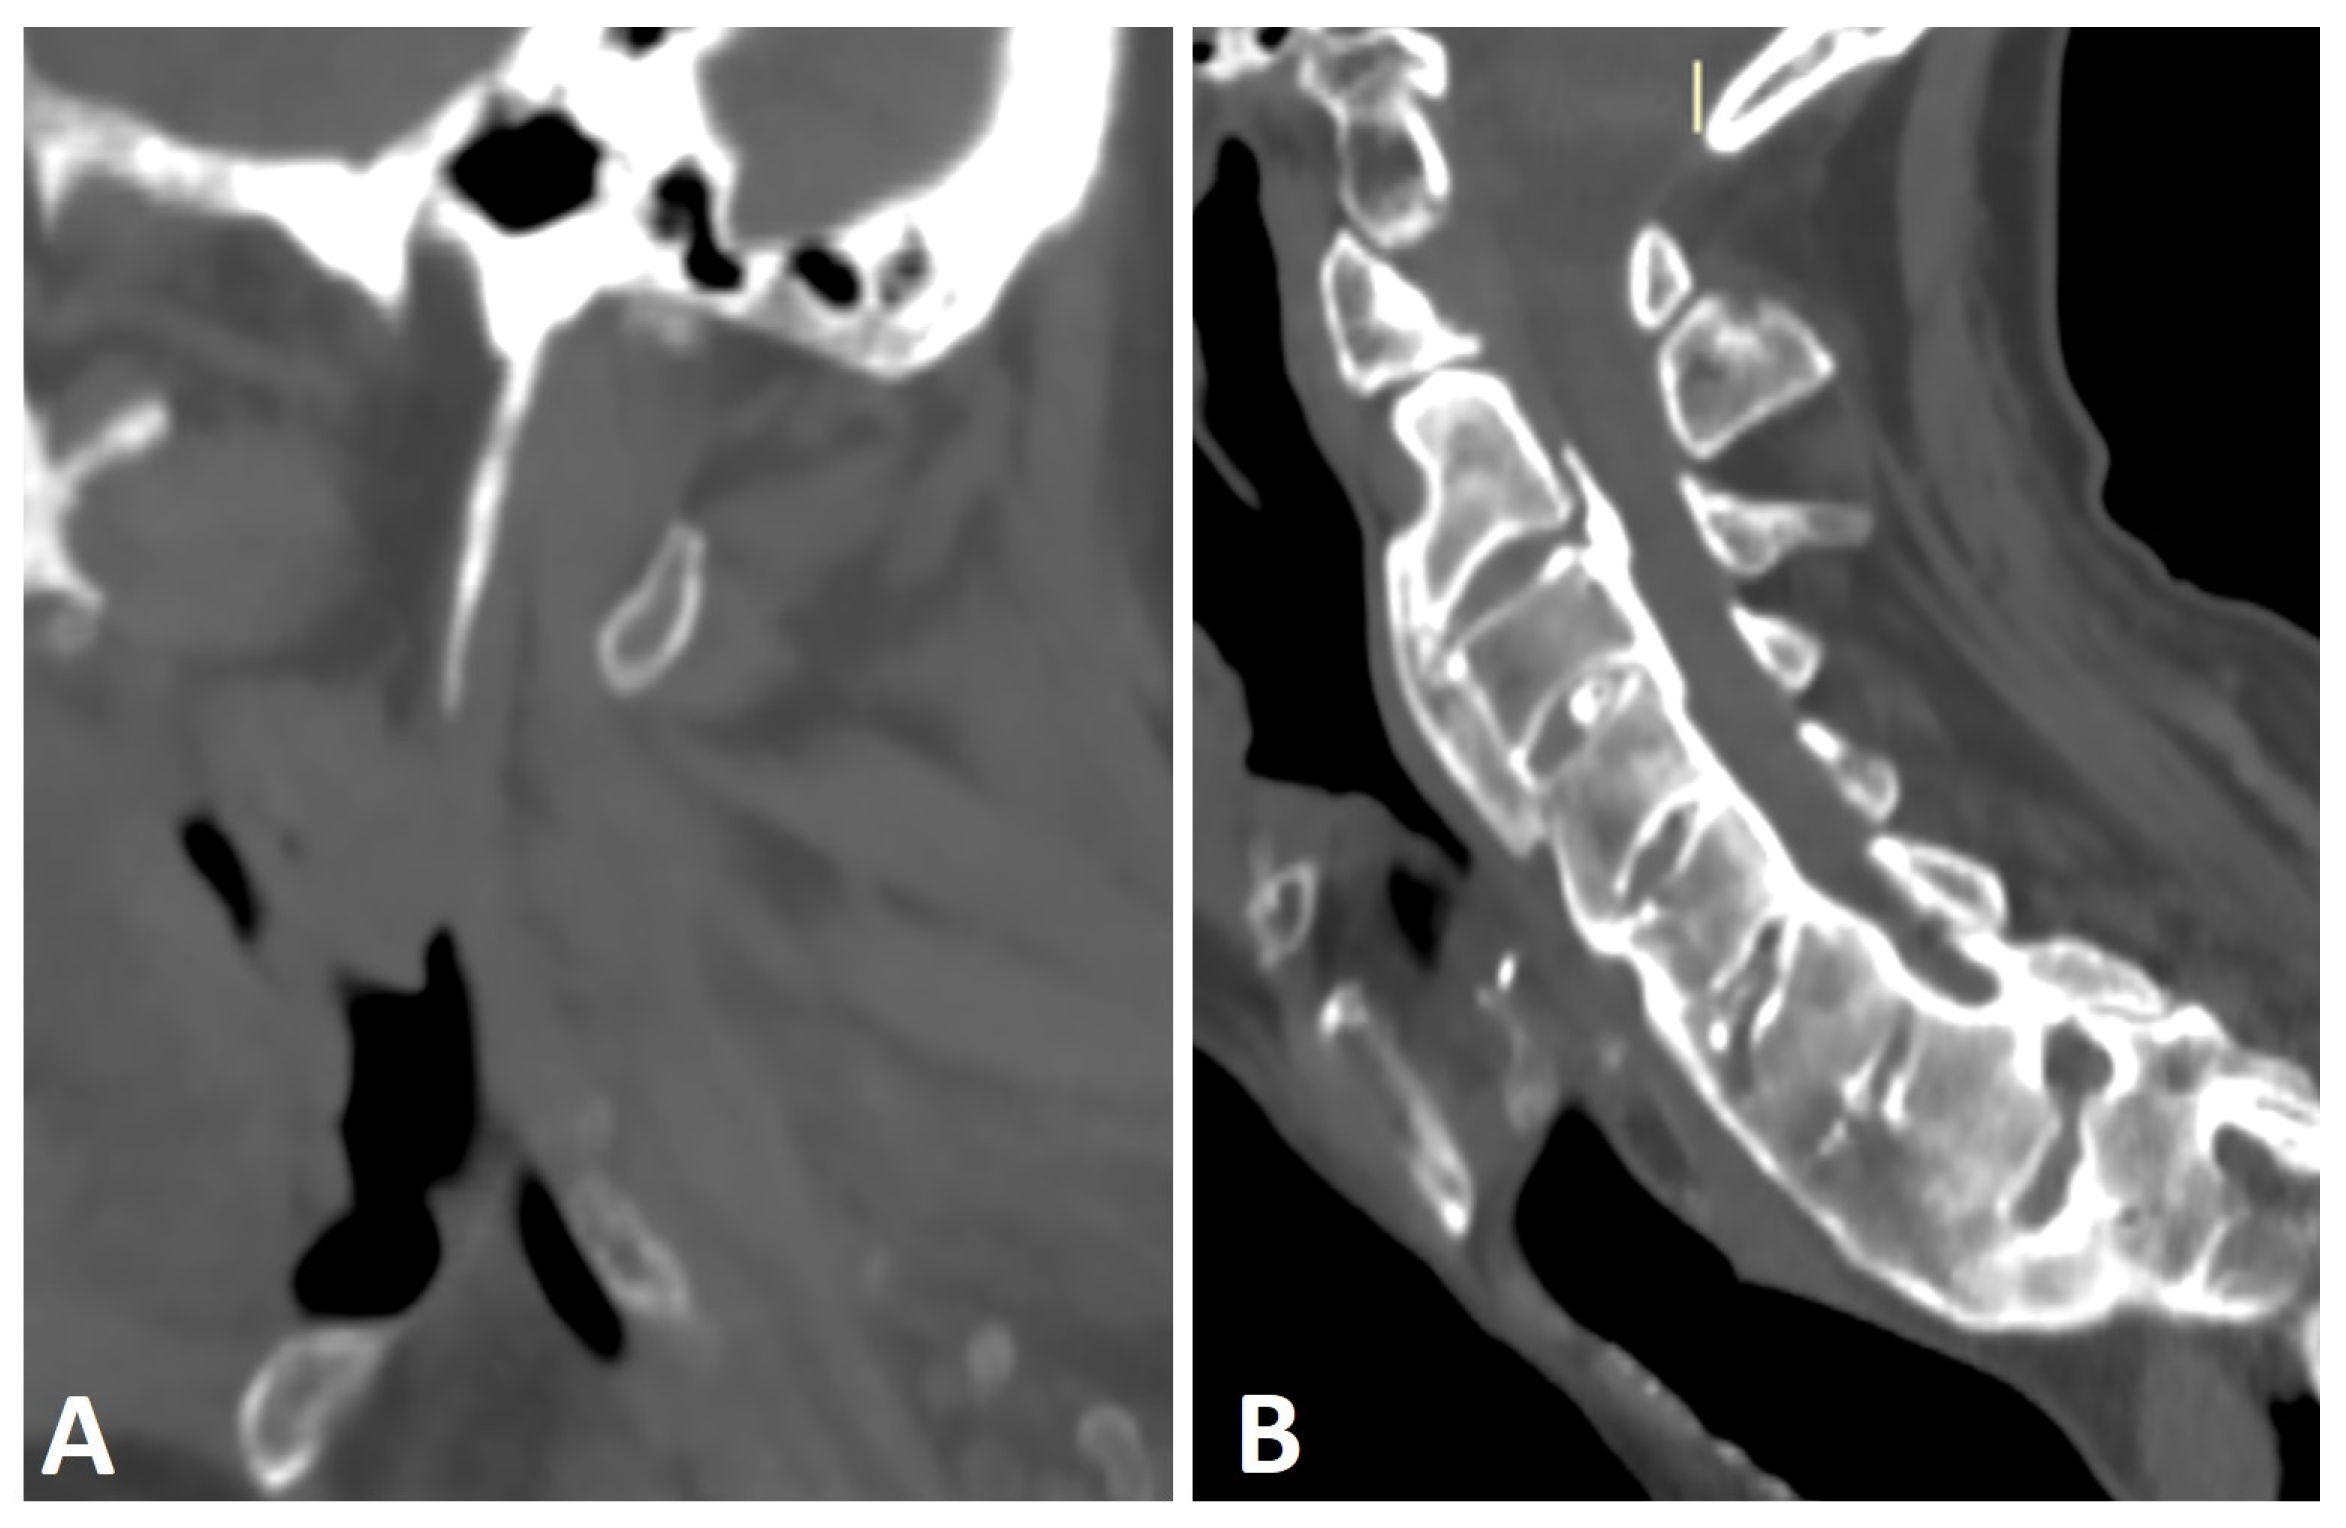

Figure 4.

Sagittal CT reconstructions of the cervical spine of two patients with thoracic DISH (not shown). (A) The elongated styloid process results from calcification and ossification of the stylohyoid ligament. (B) Flowing osteophytes characteristic of DISH accompanied by OPLL.